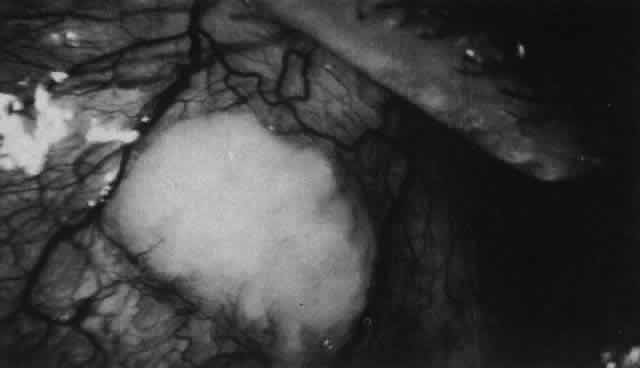

changes of scleral edema or necrosis. The onset of scleritis is usually gradual, building up over several days. By the time patients seek advice, the clinical types can be distinguished as anterior or posterior, or occasionally both. Anterior scleritis may be further subdivided into diffuse, nodular, or necrotizing. The last condition may present with signs of inflammation or with few or no signs of inflammation (scleromalacia perforans). Long-term follow-up of patients with scleral disease showed that only 8% of patients changed from one type of disease to another during the course of this disease, so although differentiation into these types does not usually indicate an etiology, it does have a direct bearing on the prognosis and the type of treatment to be used.10 Scleritis is most common in the fourth to sixth decades of life and occurs more frequently in women than men (8:5). Necrotizing scleritis occurs later than the other varieties, the mean age being 61 years. Scleritis is bilateral in 52% of patients. In half of these, the condition starts in both eyes simultaneously, with the rest becoming bilateral in 5 or more years. ASSOCIATED SYSTEMIC DISORDERS In a review of 1200 patients with scleritis who have attended the Scleritis Clinic at Moorfields Eye Hospital in London, an associated systemic disorder was found in all patients with scleromalacia perforans, in half of those with nodular and necrotizing disease, in a third of those with diffuse anterior scleritis, and in only 10% of those with posterior scleritis. Severe polyarticular rheumatoid arthritis and a case of porphyria accounted for the patients with scleromalacia perforans. Forty percent of the patients with necrotizing scleritis had other connective tissue disorders, but, surprisingly, only 21% of the patients with diffuse anterior or nodular scleritis had rheumatoid arthritis or other connective tissue disorders. This percentage is much lower than that reported by other authors,7,11–13 but this may be because patients with the less severe scleral disease are referred to us only if the etiology is in doubt, thus biasing the results. Twelve percent of the patients with diffuse anterior and nodular scleritis had ankylosing spondylitis, and in a further 15% the scleritis followed an attack of herpes zoster ophthalmicus. A variety of other conditions, including syphilis, tuberculosis, gout, Reiter's disease, IgA nephropathy, and erythema nodosum, were thought to be definite etiologic factors because with appropriate treatment the eye changes disappeared. Fowler investigated a random selection of the patients with scleritis at Moorfields Eye Hospital and found only 7%, all of whom were young males, who did not have any other detectable physical abnormality.14 Forty percent of these patients had hypertension, which in some cases required treatment. It was thought that the hypertension could have been a manifestation of a generalized arteritis, but this was convincingly demonstrated in only 19% of these patients. PATHOLOGY The pathology of scleritis has received much attention in the past.6,8,15–19 Although certain inferences can be drawn from pathologic specimens of eyes removed because of pain, perforation, or mistaken diagnosis, these eyes have been severely damaged from advanced disease. Unfortunately, biopsies of scleral lesions have proved to be unsatisfactory, at best yielding material of limited diagnostic value and at worst leaving an area of exposed choroid that will not heal. Consequently, they should not be performed. Scleritis usually affects the anterior segment of the eye, possibly because this is the area with the best blood supply, but with sluggish flow through the vessels (Fig. 19). The sclera is thickened and roughened in the affected area, which appears to be sharply demarcated from the rest of the sclera. However, tissue obtained at surgery during the course of grafting of areas adjacent to necrotic tissue shows marked pathologic changes.20,21 The area of affected sclera may be swollen, excavated, or frankly ulcerated with undermined edges covered with a thin layer of fibrous tissue. However, spontaneous perforation is extremely unusual and, where seen in pathologic specimens, has usually occurred at the time of removal of the eye. A posterior scleritis often occurs as an extension of anterior disease; but, as in Figure 20, most of the inflammation (in some cases all of the inflammation) is in the posterior segment and the exudative detachments and subretinal granulomas can be mistaken for malignant melanoma.

What is clinically represented solely by inflammation and edema is histopathologically a granulomatous lesion of the sclera, the center of which consists largely of plasma cells, lymphocytes, and mast cells (Figs. 21 through 23). Foster and colleagues have identified the cellular subsets and glycoproteins in both necrotizing and non-necrotizing scleritis.22 This shows an active T-cell inflammatory response with a high CD4/CD8 ratio and increased HLA/DR and CD14, indicating a macrophage-induced response that would lead to granuloma formation. Remote from the granuloma, the fibrocytes of the sclera become activated, the proteoglycan adjacent to them becomes altered, and the collagen fibrils of the sclera become unraveled (Figs. 23 and 24). These changes appear to take place prior to the invasion of the stroma by cells of the granuloma.20 The vessels in and around the necrotic area show medial necrosis and perivascular cuffing with lymphocytes, and endothelial swelling with microvascular occlusion. Ninety-six percent of the specimens examined by Foster and associates show a microangiopathy characterized by a neutrophil infiltrate in and around the vessel wall.22–23 This is most obvious at the center of the lesion where there may be occlusion of the vessel, thrombosis, or even aneurysm formation (Fig. 25). From these pathologic investigations, clinical observations, animal experiments, and the results of fluorescein angiography, it would appear that the scleral inflammation is initiated either by trauma (be it accidental or surgical)23–25 or by bacterial or viral infection. If circulating immune complexes are present because of the poor blood flow, they become precipitated in and around the vessel walls in the area of inflammation. In other patients, a persistence of tissue damage will lead to autoimmunization. Damage to the endothelial cells of the microvasculature leads to changes within the vessels detectable on angiography and to catabolic changes in the surrounding tissues. These changes, in turn, allow the granulomatous response that is seen in histopathologic sections, the first detectable change being in the scleral fibrocytes and the proteoglycan and collagen remote from the site of cellular infiltration.